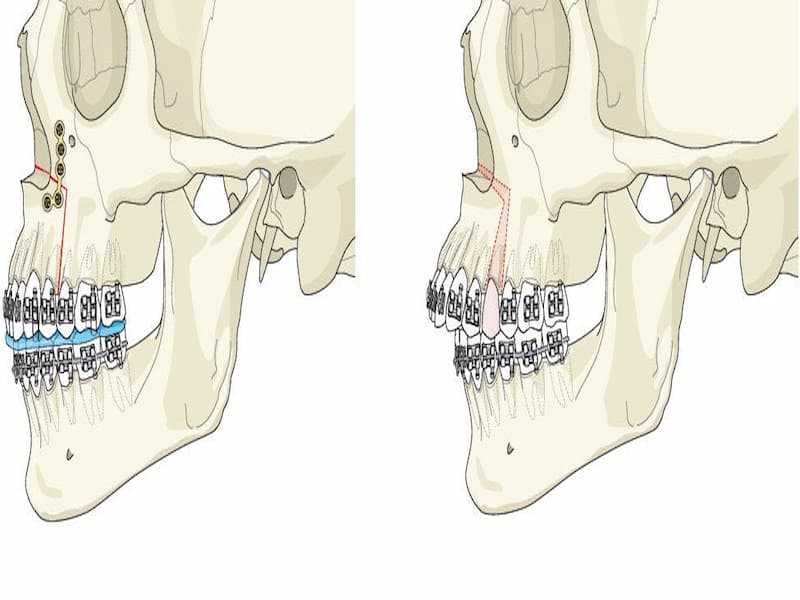

اصولا دندان پزشکان برای انجام ایمپلنت قبل از هر کاری سطح لثه را جراحی می کنند تا بتوانند ایمپلنت را در جای مناسب قرار دهند.

ایمپلنت از جنس فلز بوده و ظاهری همانند پیچ را دارا می باشد که امروزه به اسم فیکسچر نیز در بین مردم شناخته می شود.

به طور کل محل جوش خوردن آن در فک بالا می باشد که با توجه به جای خاص آن می توانیم بگوییم پایه ای برای دندان های کشیده شده و از دست رفته در نظر گرفته می شود.

اباتمنت نیز که بر روی ایمپلنت فک بالا قرار می گیرد و جایگزینی برای تاج دندان بوده که نقش جویدن غذا را می تواند به خوبی تمام انجام دهد.